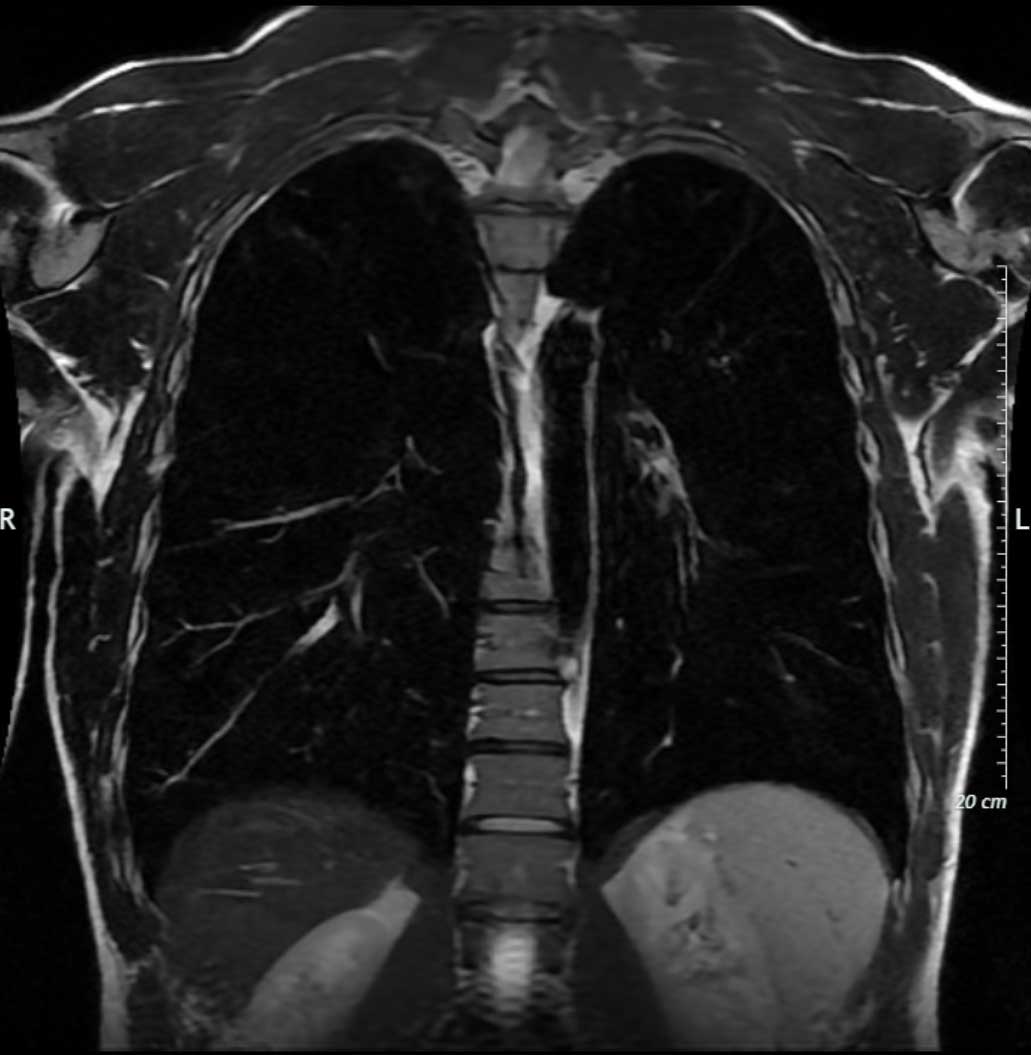

Eine MRT von Brustkorb und Thorax bietet die Möglichkeit, diese Organe, Gewebe und Gefäße in hoher Auflösung darzustellen, um Abnormalitäten, Entzündungen, Tumore, Verletzungen, Lungenpathologien und anderen Anomalien zu identifizieren und diese zu diagnostizieren.

Eine MRT bietet den Vorteil, dass sie nicht-invasiv ist und keine Strahlenbelastung wie bei Röntgen- und CT-Aufnahmen mit sich bringt. Zusätzlich können wir mittels oZTEo CT-ähnliche Bilder generieren